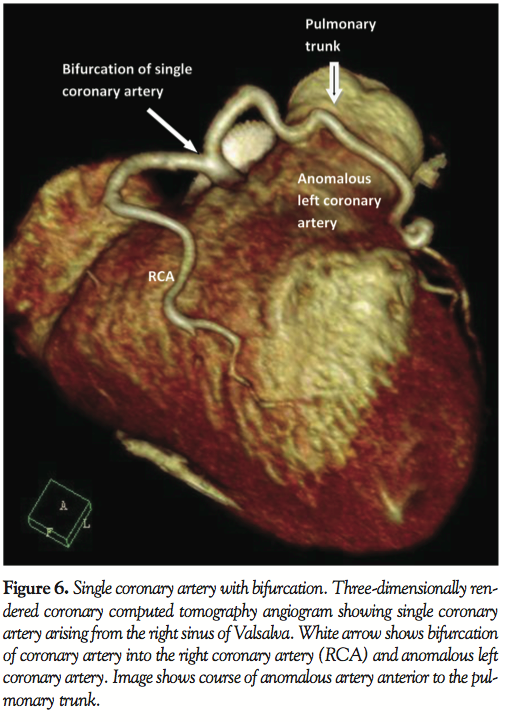

A 59-year-old man with a history of hypertension, family history of premature coronary artery disease and atypical chest heaviness was referred to exercise stress test. After achieving 89% target heart rate at a workload of 9 metabolic equivalents using Bruce protocol, 1–1.5 mm horizontal ST depressions were seen in the lateral leads. Coronary angiogram revealed a single coronary artery originating from the right sinus of Valsalva; this artery bifurcated into a right coronary artery and an anomalous left main coronary artery. Multi-detector row computed tomography confirmed the same findings. The anomalous left coronary artery followed a pre-pulmonary course anterior to the pulmonary trunk to supply the anterior descending, diagonals and circumflex artery. There was no evidence of an inter-arterial course, which is considered malignant. The coronary arteries were free of atherosclerotic disease. Stress myocardial perfusion imaging showed no inducible ischemia. Echocardiogram showed normal left ventricular function.